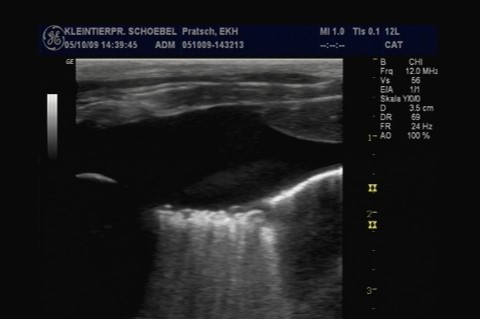

Echokardiografie (Herzultraschall)

Die Echokardiographie ist eine Ultraschalluntersuchung des Herzens. Sie ermöglicht eine bildliche Darstellung des Herzinneren, der Herzmuskeldicke und ist die einzige Untersuchungsmethode, in der die Herzaktionen, d. h. die Pumpfunktion von Herzkammern und -vorhöfen und die Funktion der Herzklappen beurteilt werden kann. Auch anatomische Anomalien (Persist. Ductus Arteriosus, Ventrikelseptumdefekt, Aortenstenose), Verwirbelungen des Blutes, Thromben, Tumore oder Herzbeutelergüsse werden hiermit diagnostiziert.

Die Bildqualität und damit die Qualität der Untersuchung ist stark abhängig von der Qualität des Ultraschallgerätes und der verfügbaren Sonden. Mit unserem Ultraschall- Doppler „Philips Affinity“ steht uns ein modernstes und hochwertiges High-End- Ultraschallgerät der neuesten Generation zur Verfügung. Wir verwenden für Hunde und Katzen unterschiedliche hochauflösende Ultraschallsonden um beste Bildqualität zu gewährleisten.